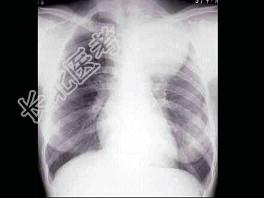

- 单项选择题女,25岁, 胸背痛半月余,胸片如图, 最可能的诊断为 ( )

A、左上肺不张

B、左上肺炎

C、纵隔肿瘤

D、左上肺癌

E、左上肺炎性假瘤